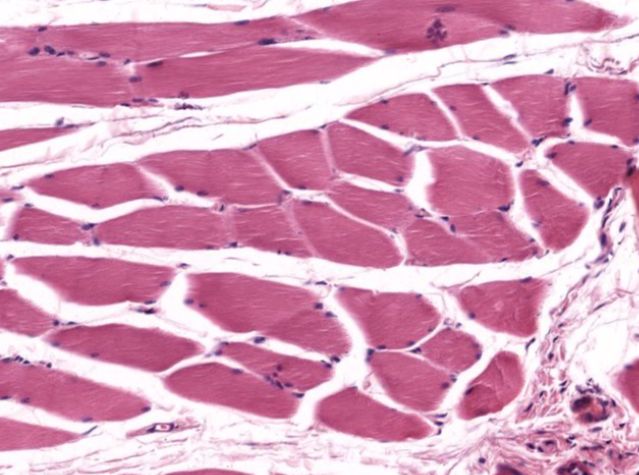

Cross Section β€” Slide 058-T Β· H&ENow you are looking at the cut face of the same cylinders. Each circle is one fiber. Find the nuclei at the rim, count the fascicles, and trace the CT wrappings from innermost to outermost.

Skeletal muscle cross section H&E

Skeletal muscle β€” cross section Β· H&E Β· Slide 058-T Β· University of Michigan Histology (CC BY-NC-SA 3.0)

Click each numbered chip to reveal the labeled structure

DMD results from a mutation in the dystrophin gene. Dystrophin links the sarcolemma to the internal cytoskeleton, stabilizing the membrane during contraction. Without it, the sarcolemma tears repeatedly, calcium floods the cell, and the fiber degenerates. On H&E, affected muscles show fibers of wildly variable size, centrally-relocated nuclei (a regeneration sign), and replacement by fat and CT. The peripheral nucleus you just labeled? Its position is the first thing that changes in a diseased fiber.

In a cross-section, a student points at dots near the centers of fiber circles and calls them nuclei. Are they correct? What's the giveaway?

AnswerNo β€” skeletal muscle nuclei are peripheral, pushed to the outer edge. Central nuclei indicate cardiac muscle or a regenerating/diseased skeletal fiber. If you see central nuclei in skeletal muscle, that is a diagnostic red flag.